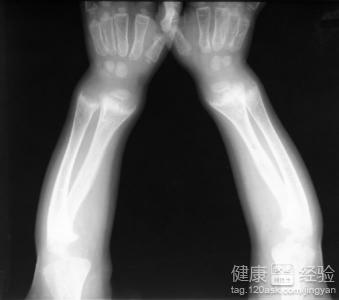

2小兒生長最快的部位就是骨骼,但同時也是最脆弱的部位。如果得了佝偻病,容易出現方顱、漏斗胸、腳镯症、O型腿、X型腿、脊柱側彎等症狀。為了預防這種骨骼的病變,家長應該耐心的為孩子穿衣服,有一張舒適整潔的床提供他們休息,避免太早、太久地坐、站、走,以免發生骨骼畸形。

3佝偻病的診斷還可以通過一系列的檢查去查看小兒的情況。生化檢查可以查看血鈣的變化和X線檢查可以查看骨骼的形狀。一旦發現異常情況,及時進行治療。用藥物或矯正的方法,避免病情的繼續惡化。嚴重的可以根據醫生的安排進行外科的手術。